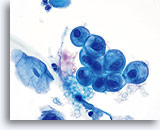

Tubal Metaplasia

Tubal metaplasia is characterized by columnar cells with pleomorphic, hyperchromatic nuclei with increased N/C ratios. As with conventional Pap smears, cells from tubal metaplasia may occasionally be mistaken for atypical endocervical cells and even adenocarcinoma in situ. In order to avoid an over-diagnosis, look for the presence of discrete cytoplasmic vacuoles, terminal bars and cilia.